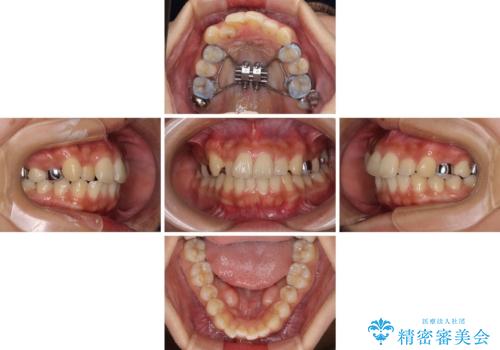

- 矯正装置

- インビザライン

上顎骨の幅が下顎骨よりも小さいので、拡大装置により骨幅を広げて上下関係を改善し、その後インビザラインにて歯並びを整えることとしました。

上下の骨幅を改善したことで、スムーズに歯列矯正を行うことができました。

土台のまま放置されていた歯は土台の状態で咬み合っていましたが、急速拡大を行った際に咬み合わせが著しく挙上されたため、その際に土台を大きくすることで咬み合う歯との距離を確保しました。